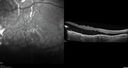

58 year old female The patient noticed decreased vision in the right eye about 2.5 months ago. (you may want to omit this initially -> ) 3 months ago she found a lump in her breast and had stage IV cancer which had spread. It is in her bone, lung. She is starting radiation tomorrow on a couple of vertebrate. Medical Hx: (Onset: 3/28/2023). Breast Cancer Stage 4. Hypertension, Systemic. Surgical Hx: Tonsillectomy. C-Section. Systemic Meds: Propranolol Hydrochloride, 80 mg oral tablet qday. PROCHLORPERAZINE 10MG qday. ANASTROZOLE 1 mg ORAL TABLET, FILM COATED [Anastrozole] qday. Dexamethasone 400 MCG/0.1ML PFS qday. VA OD: Dcc20/200 VA OS: Dcc20/63 IOP: TP: OD:12 OS:15 Put breast cancer history here: Had 10 sessions of radiation to the right eye starting 4/2023 and ending 04/26/23. Also - 4/2023 - kisqali and letrosole (forever drugs) 12/12/23 - Retinal detachment almost completely resolved – Exudative RD took 8 months to resolve. – VA improved from 20/200 to 20/40 (last visit)

Choroidal Metastatic Breast Cancer with Exudative Detachment109 views58 year old female presented with 20/200 vision. Had 10 sessions of radiation and tumor shrank. The exudative detachment took almost a year to resolve. The vision improved to 20/40.00000